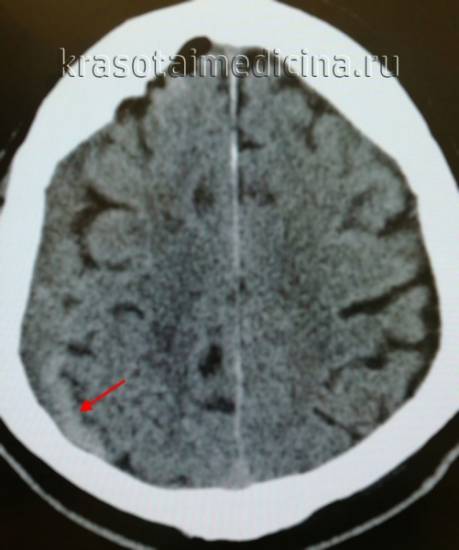

Ключевыми методами диагностики субдуральной гематомы являются КТ и МРТ головного мозга. Для острых гематом предпочтительнее КТ, которая выявляет однородную зону повышенной плотности серповидной формы. Со временем гематома разуплотняется, и через 1-6 недель она перестает отличаться по плотности от окружающих тканей. В таких случаях диагноз основывается на смещении латеральных отделов мозга в медиальном направлении и признаках сдавления бокового желудочка.

КТ-скан, демонстрирующий субдуральную гематому.

На компьютерной томографии субдуральные гематомы имеют классическую серповидную форму, но могут выглядеть и линзовидно, особенно в начале кровотечения. Это может затруднить дифференциальную диагностику с эпидуральными гематомами. Более надежным признаком субдуральной гематомы является её широкое распространение по полушарию головного мозга с преодолением швов черепа. Субдуральная гематома может также выглядеть как «наслоение» повышенной плотности вдоль намёта мозжечка; такая гематома может быть хронической и стабильной, а косвенными признаками кровоизлияния служат сглаженность прилегающих борозд и медиальное смещение границы между серым и белым веществом.

Хронические гематомы на компьютерной томографии могут не дифференцироваться из-за изоденсивности с мозговым веществом, что затрудняет их выявление.